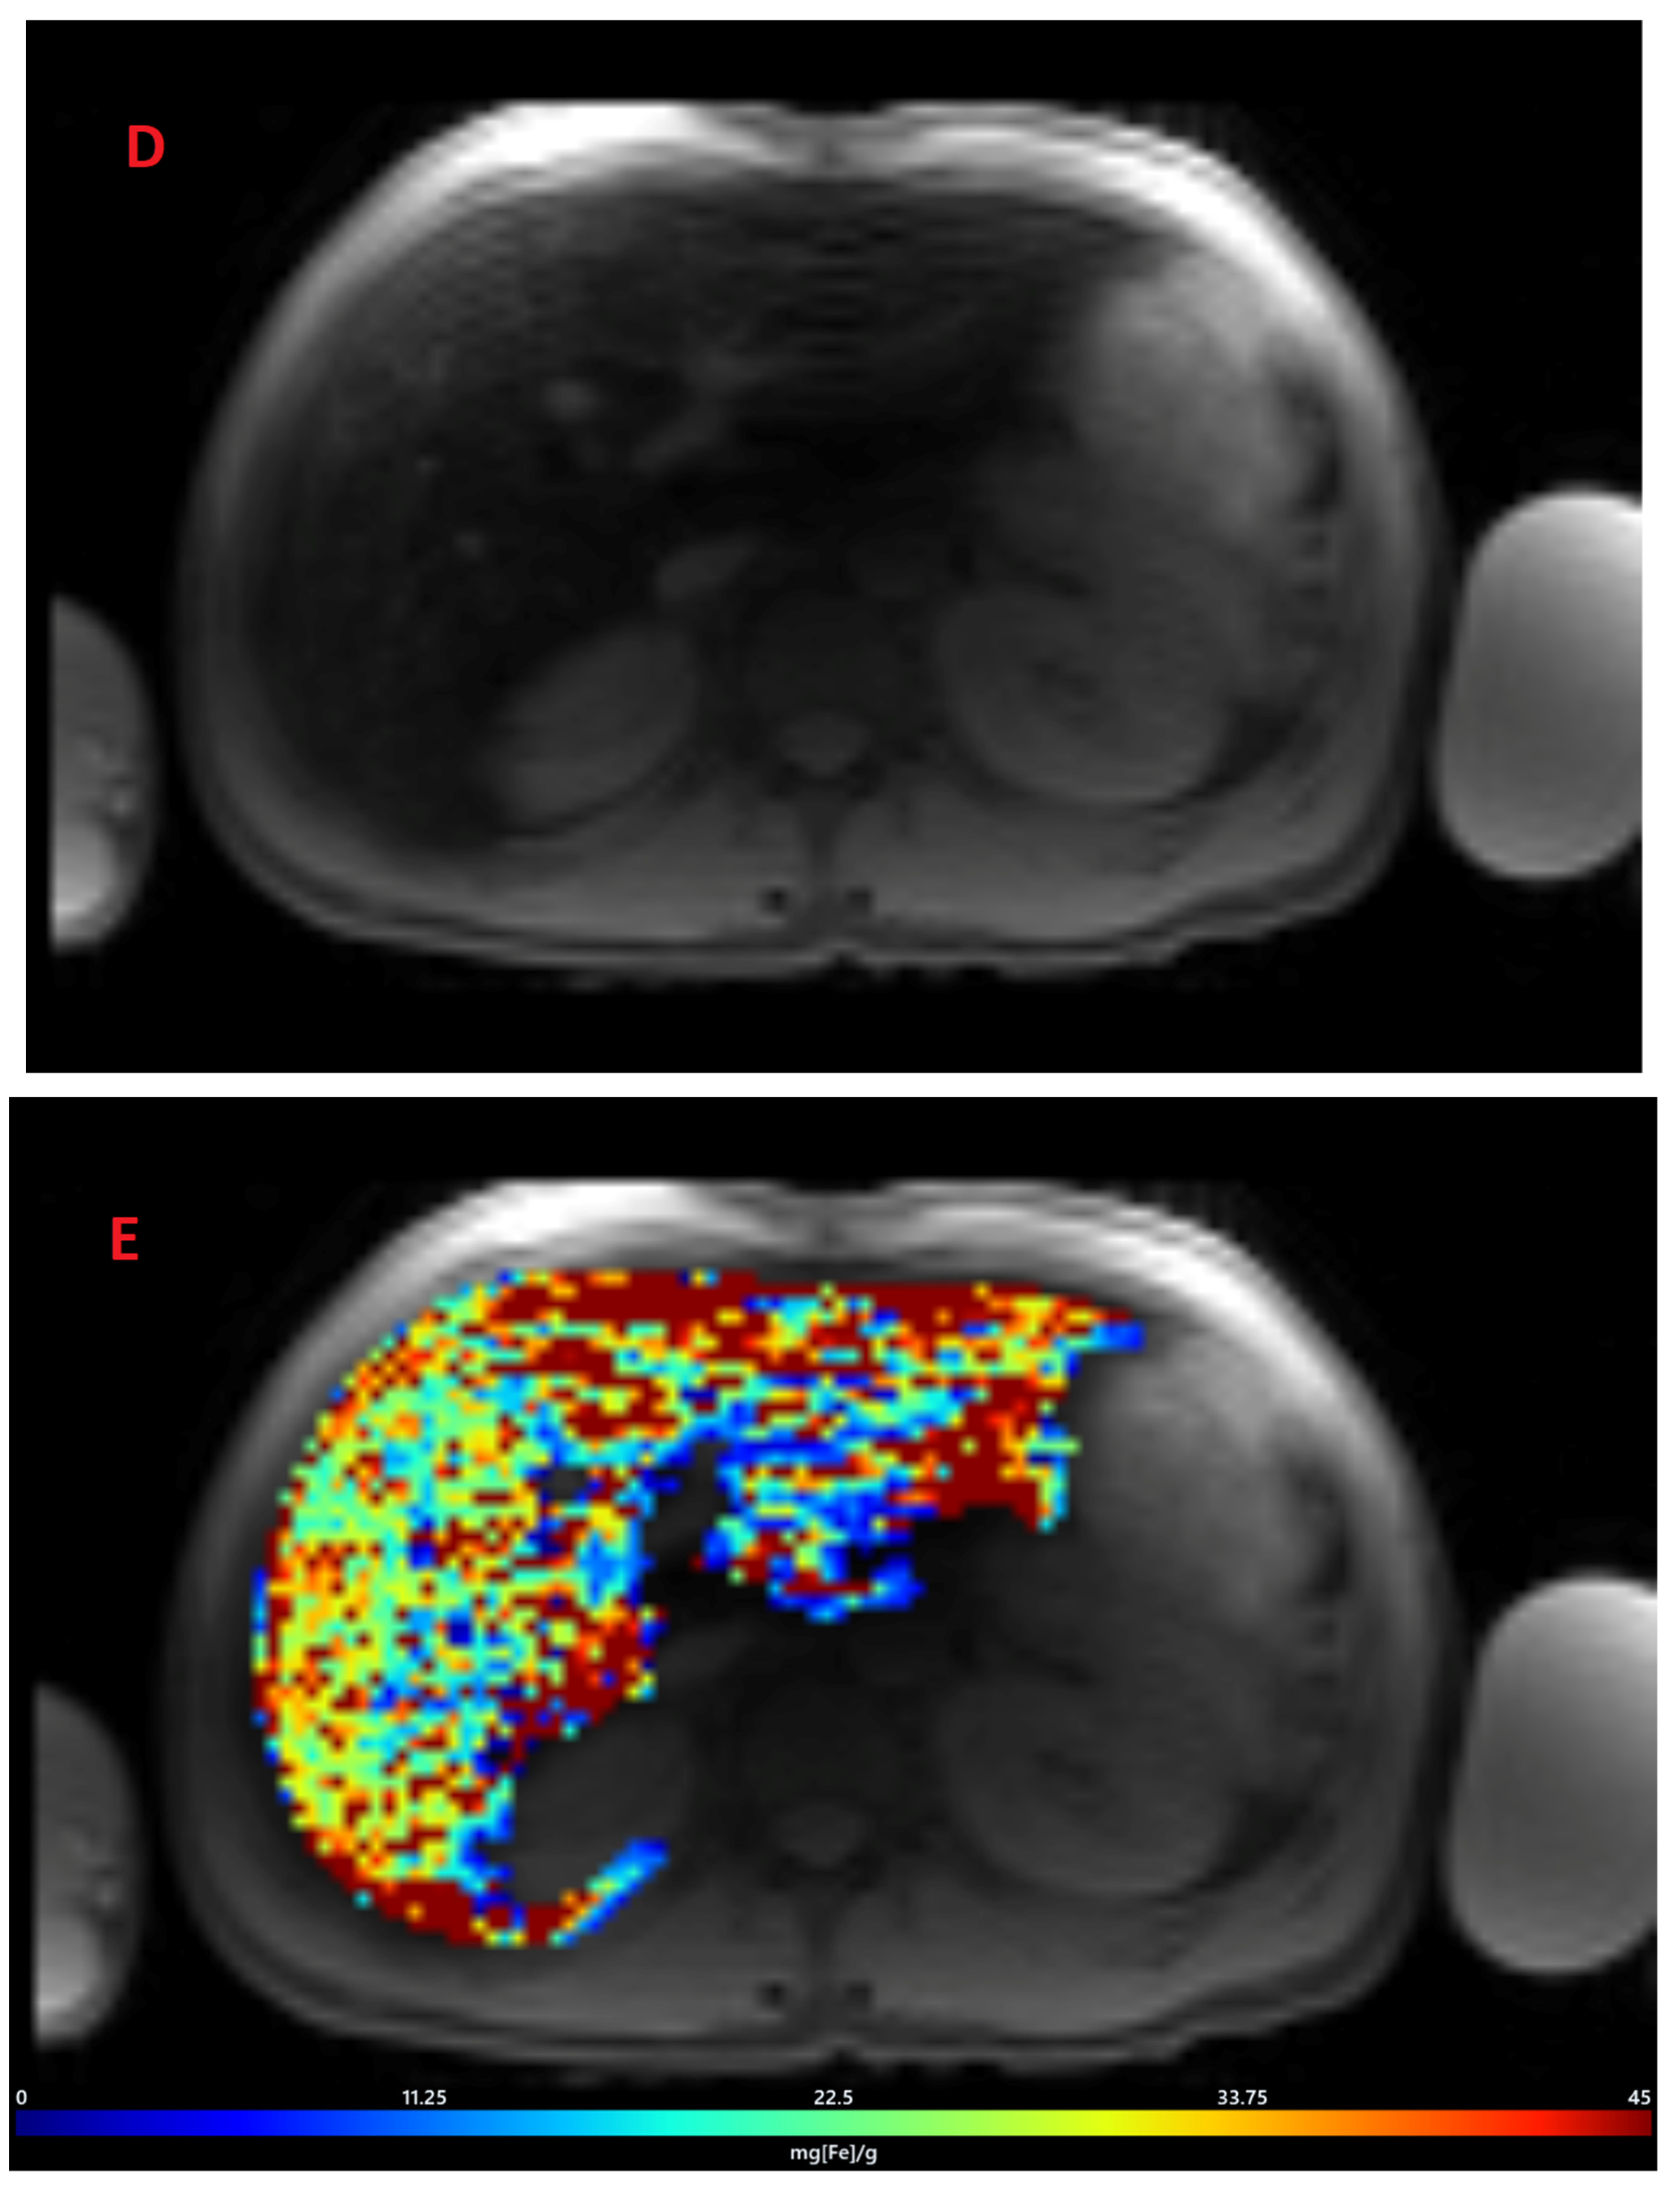

3.1. Estimation of LIC by R2 Relaxometry (LIC R2)

3.2. Estimation of LIC by R2* Relaxometry (LIC R2*)